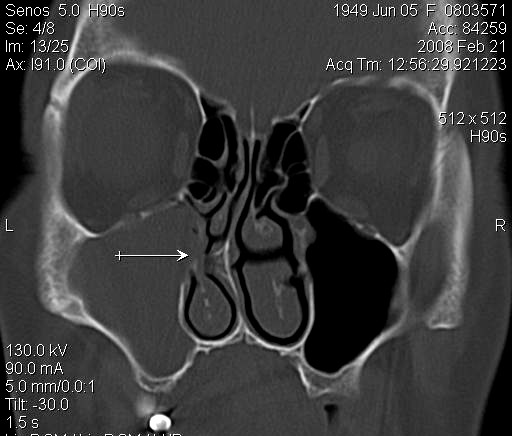

JFC Sinusitis maxilar. Espolón septal.